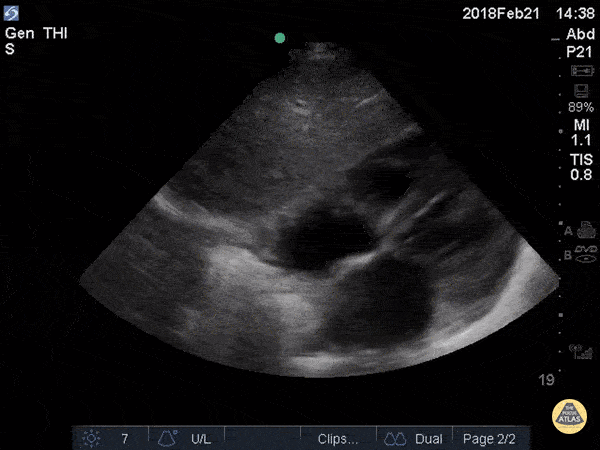

Trauma - Subxiphoid

The most superficial structure we see is the liver. Immediately deep to that we see the heart separated from the liver by the diaphragm. Closest to the liver is the right atrium, tricuspid valve, and right ventricle. Deeper to that, we see the left atrium, mitral valve, and left ventricle. There is no anechoic fluid between the bright hyperechoic pericardium and the myocardium, indicating absence of pericardial effusion. Hannah Kopinksi and Dr. Lindsay Davis - NYU Emergency Medicine